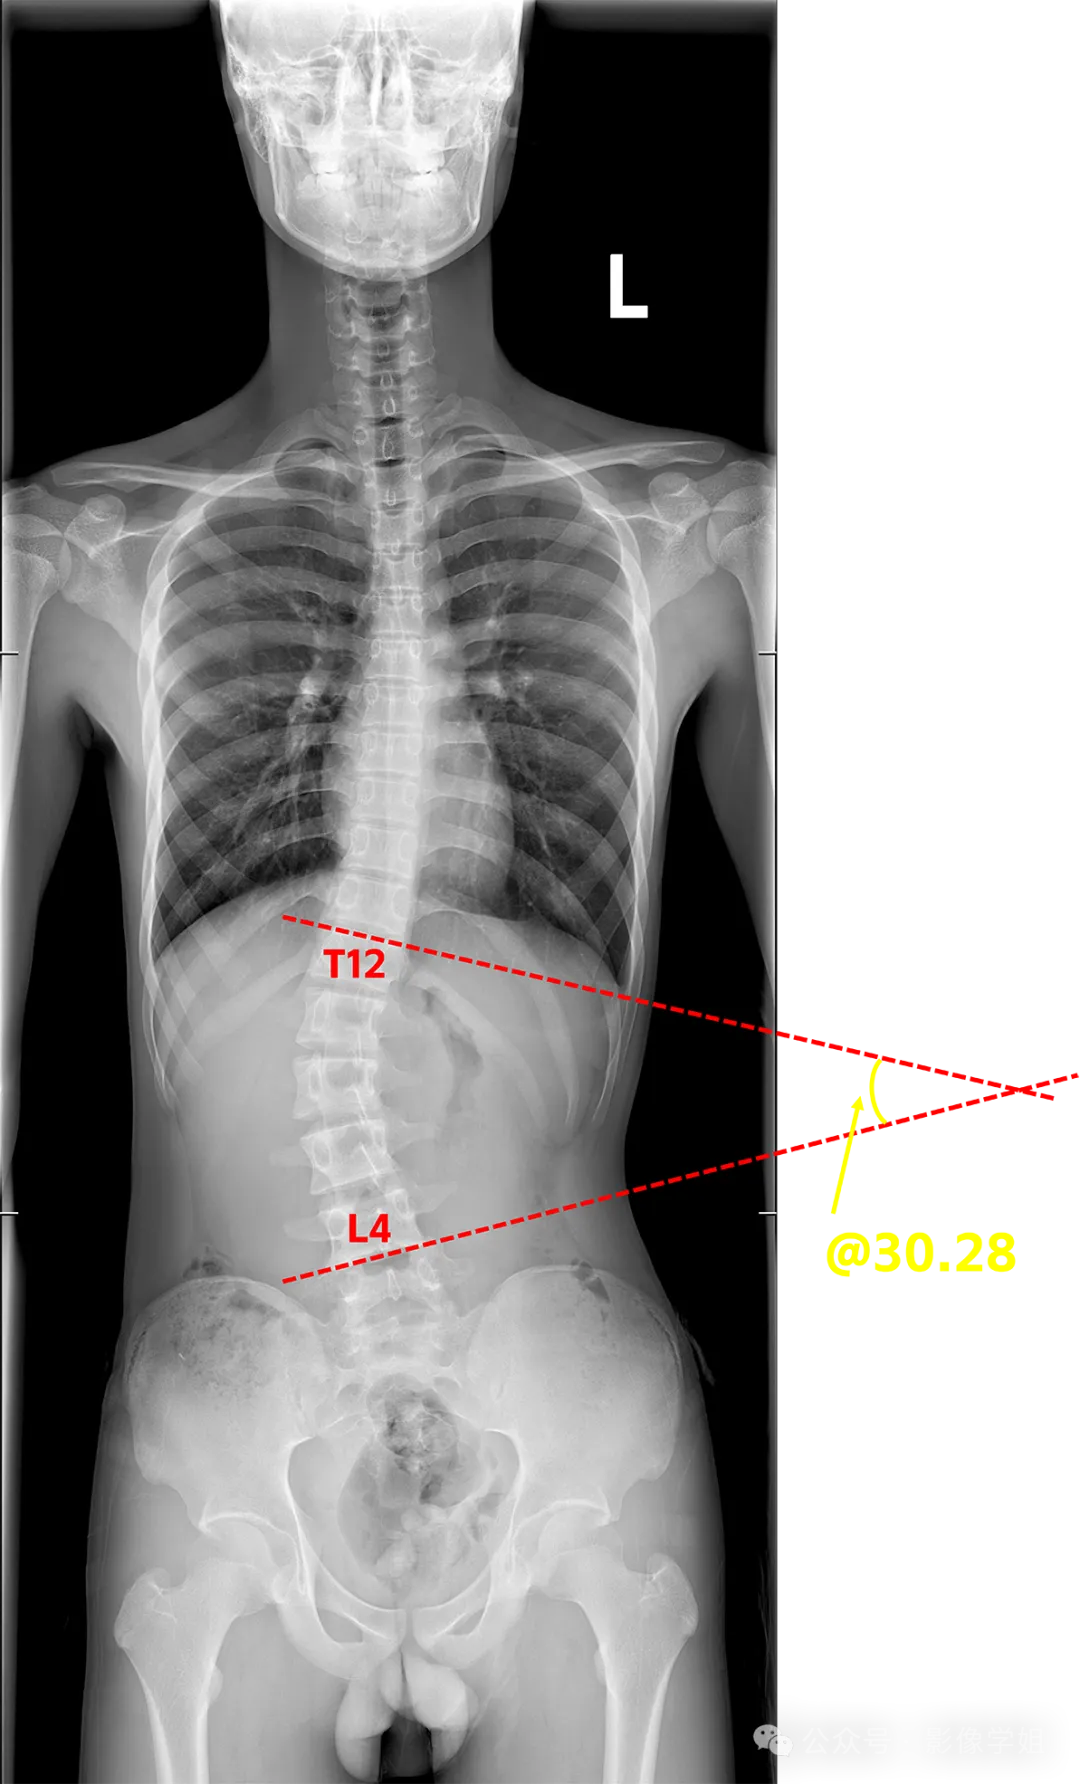

美式整脊具有一系列检查方式,进行脊椎物理检查,体态及关节活动分析,神经反射检测,以及全脊椎X光片,整体力学,功能分析,制定治疗方案。